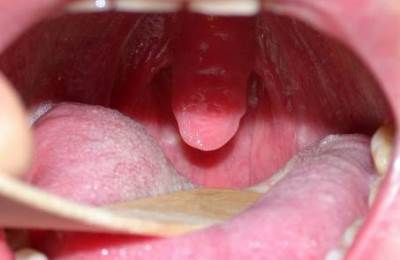

Запалення язичка найчастіше спостерігається при захворюваннях горла.

Для цього знадобиться дзеркало (бажано, збільшує), і хороший джерело світла. При вивченні ротової порожнини можна помітити, що конічний відросток збільшився в розмірах — причому, не тільки опух, але і став довшим.

- виражена набряклість, значне провисання язичка;

- Подовження піднебінного язичка.

- Гіперемія органу. Він стає червоним із-за інтенсивного припливу крові.

При увулите піднебінний язичок спочатку червоніє, потім поступово набрякає, розпухає. Захворювання розвивається стрімко.

Візуально ви можете побачити, що язичок придбав яскраво червоний колір. Це обумовлено тим, що в ньому є безліч кровоносних судин, які часто запалюються. Також він звисає до кореня мови.

Також хвороба розвивається при наявності аденоїдів. Якщо при запаленні поглянути в горло, то можна побачити яскраво-червоний піднебінний язичок, який почав звисати до кореня мови. Поряд з цим опухає і болить м’яке небо.